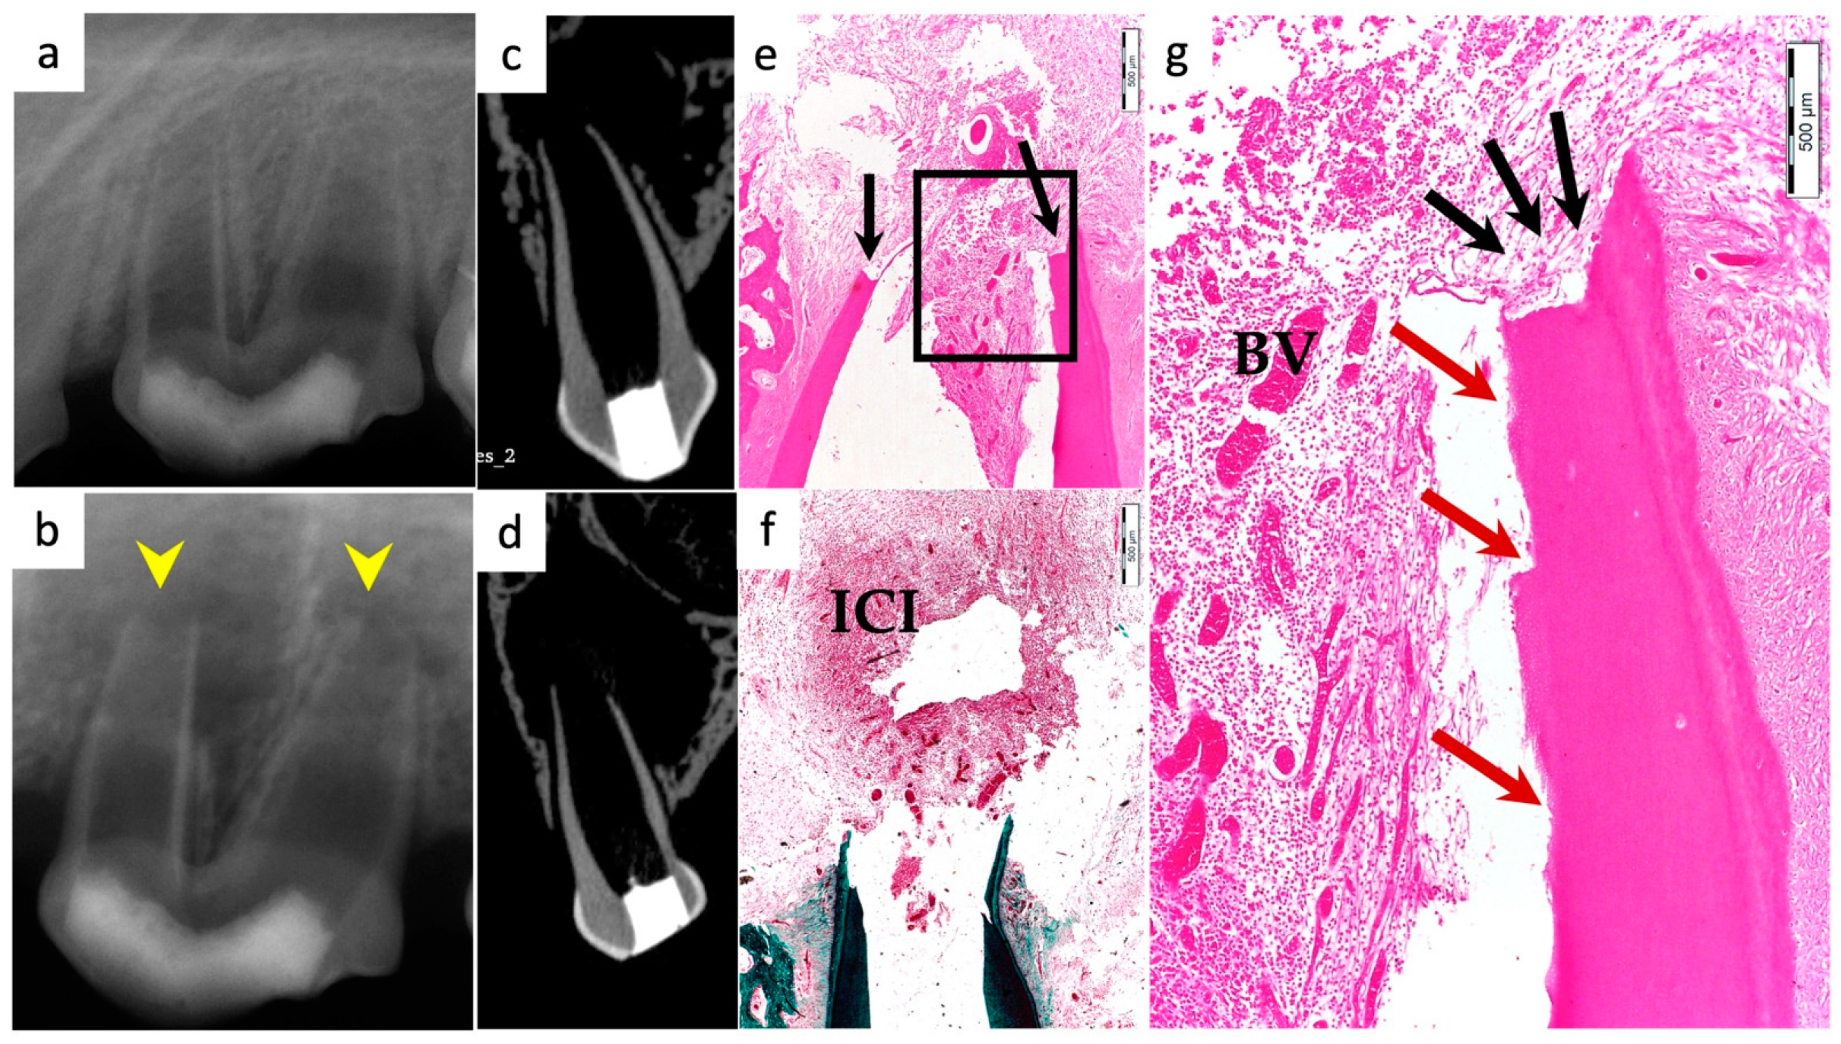

3.6. Positive and Negative Control Groups